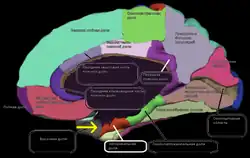

Большие полушария

Головной мозг разделён бороздой на два больших полушария (Hemisphaerium cerebri): левое и правое. В большие полушария входят: кора большого мозга (плащ), базальные ганглии, обонятельный мозг и боковые желудочки. Полушария мозга разделены продольной щелью, в углублении которой содержится мозолистое тело, которое их соединяет. На каждом полушарии различают следующие поверхности:

- верхнебоковую, выпуклую, обращенную к внутренней поверхности свода черепа;

- нижнюю поверхность, расположенную на внутренней поверхности основания черепа;

- медиальную поверхность, с помощью которой полушария соединяются между собой.

В каждом полушарии есть части, которые наиболее выступают: впереди, — лобный полюс, сзади — затылочный полюс, сбоку — височный полюс. Кроме того, каждое полушарие большого мозга разделяется на четыре большие доли: лобную, теменную, затылочную и височные. В углублении боковой ямки мозга лежит небольшая доля — островок. Полушарие поделено на доли бороздами. Самая глубокая из них — боковая, или латеральная, ещё она называется сильвиевой бороздой. Боковая борозда отделяет височную долю от лобной и теменной. От верхнего края полушарий опускается вниз центральная борозда, или борозда Роланда. Она отделяет лобную долю мозга от теменной. Затылочная доля отделяется от теменной только со стороны медиальной поверхности полушарий — теменно-затылочной бороздой.

Полушария большого мозга извне покрыты серым веществом, образующим кору большого мозга, или плащ. В коре насчитывается 15 млрд клеток, а если учесть, что каждая из них имеет от 7 до 10 тыс. связей с соседними клетками, то можно сделать вывод о гибкости, устойчивости и надёжности функций коры. Поверхность коры значительно увеличивается за счет борозд и извилин. Кора филогенетическая является самой большой структурой мозга, её площадь примерно 220 тысяч мм2.